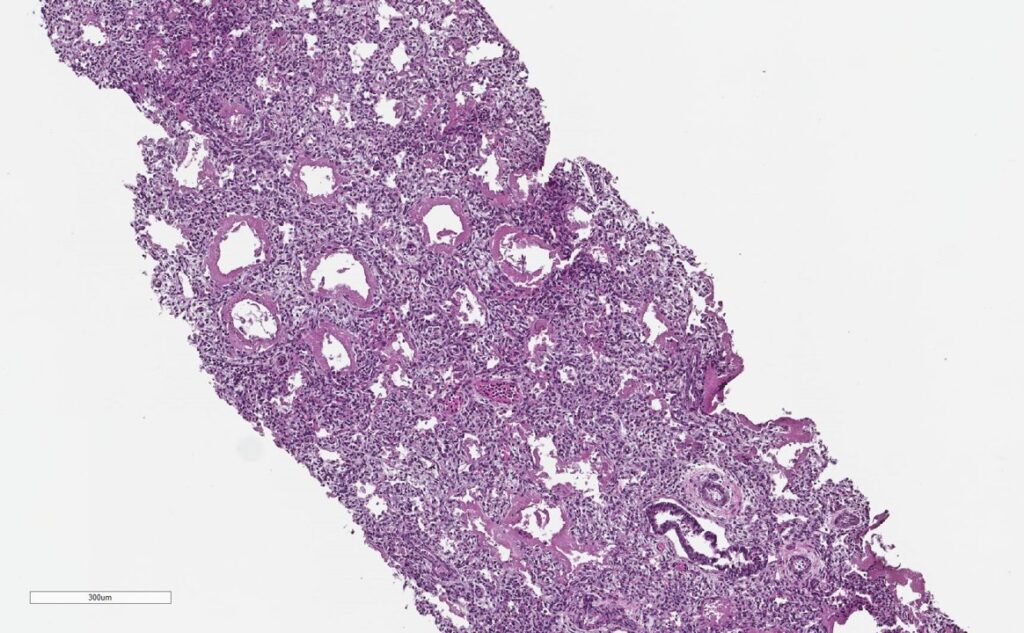

All CHAMPS laboratory results were negative for possible infectious causes of death in this case. Pathology from the baby’s right and left lungs showed severe hyaline membranes and mild interstitial inflammation, confirming the presence of RDS.

Note the thick pink membranes lining the alveolar spaces (arrows)

The CHAMPS team determined the baby died from complications of bilateral pneumothorax due to RDS. It is likely that maternal hypertension caused the premature labor.